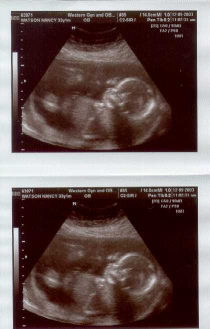

It's a girl!

Today we went to have my 19 week ultrasound and doctor's appointment. Brian stayed home from work this morning and went with me. While we waited in the waiting room Brian and I chuckled when we saw a couple came out of the ultrasound office with big smiles on their faces.

You can easily see the head as well as her little arm and even the bones in her hand.

The ultrasound technician told us the baby was a girl and that everything looked normal and healthy. The ultrasound also confirmed my due date of May 2. Now if only I can convince Brian not to name her "Bernadette".